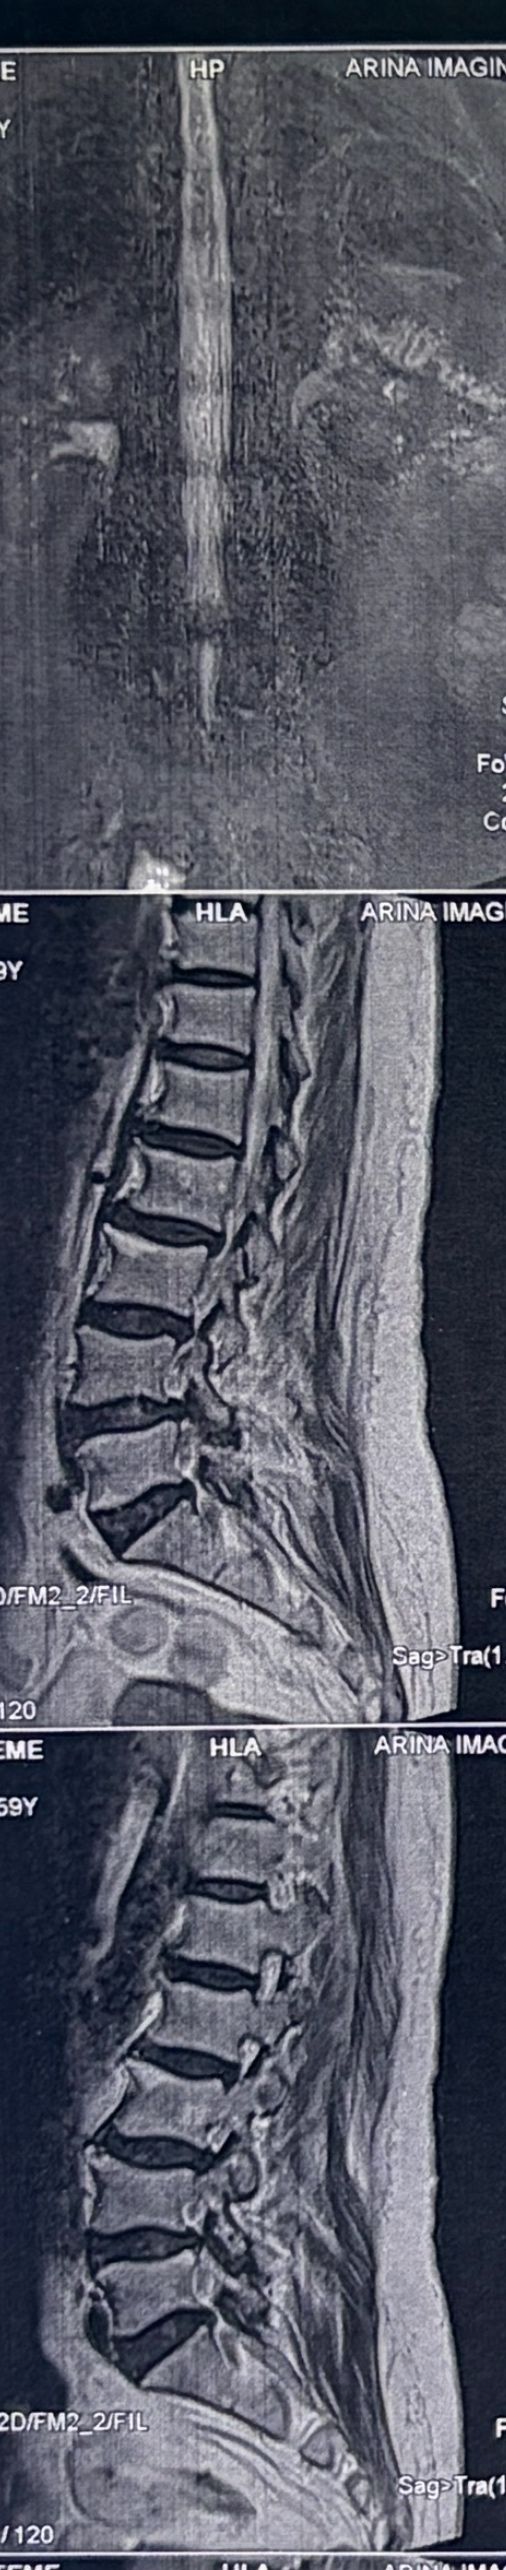

59 yrs old female just presented to my office2 hrs ago with severe R gluteal pain. No leg radiculopathy. Walking is pain free . Just aggravates by sitting. Doctors of chiropractic are able to manage these patients

What would be your plan for management? Do you adjust this patient?

Case 19

59 yrs old female today was presented to my office few days ago with low back pain in walking. Had history of fall 4 years ago which was resulted in L 3 fracture. She had sement injection in L3.

I ordered DEXA ( had osteopenia in hip) and dynamic lumbar spine x ray Please mention what would be your plan of management. If you decide to give her treatment what kind of treatment(adjustment or decompression or other treatments)whould be suitable for her? Doctors of chiropractic can decide and come up with good plan of management and treatment for these patients and are well trained when they have to refer these patients for surgery or pain management clinics. Proper selection of these kind of patients is another important fact that can be done precisely by chiropractors.